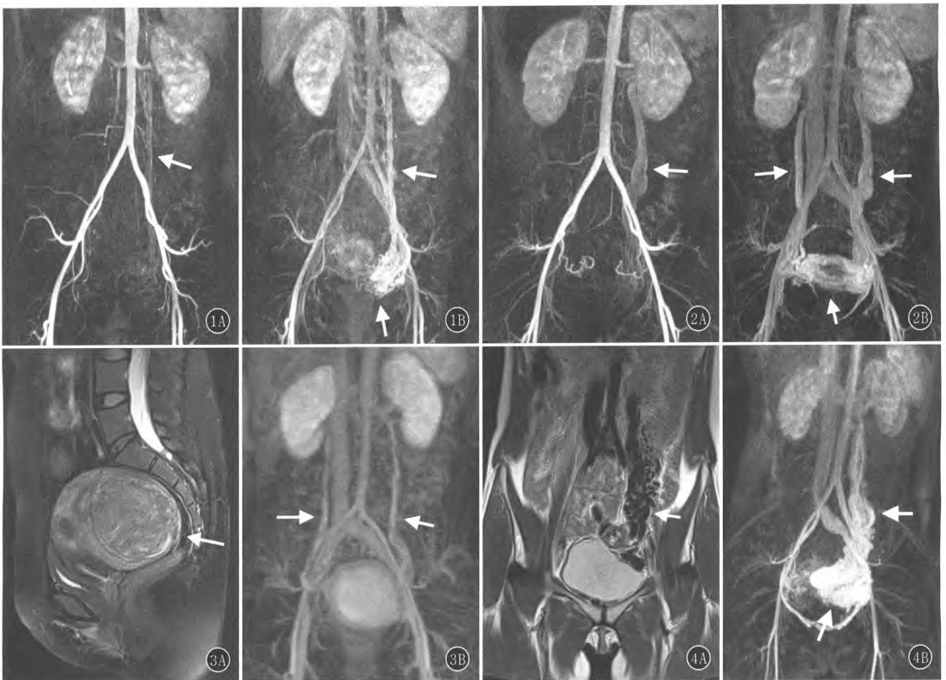

图:1A,B 女,42岁,1次生产史,6次人流史,因反复下腹痛,月经量增多前来就诊。动脉早期(A,B)反流的左侧卵巢静脉,动脉期后期见扩张的卵巢静脉与盆腔静脉相交通;图2A,B 女,26岁,因腹痛、白带增多前来就诊。A. 示左侧反流的卵巢静脉;B. 示双侧扩张的卵巢静脉和盆腔静脉;图3A,B 女,42岁,1次妊娠史,无生产史,因反复下腹痛,月经量大前来就诊。T2WI抑脂矢状位图像可见子宫后壁1个巨大占位(A),CE-MRA见双侧卵巢静脉扩张,宫旁静脉扩张;图4A,B 女,28岁,4次妊娠史,2次生产史,2014年6月滋养细胞肿瘤治疗史,2016年1月因经期大出血来院就诊。T2WI冠状位图像可见迂曲增粗的流空血管影(A),3D血管图像可见左侧卵巢静脉和宫旁静脉显著增宽(B)